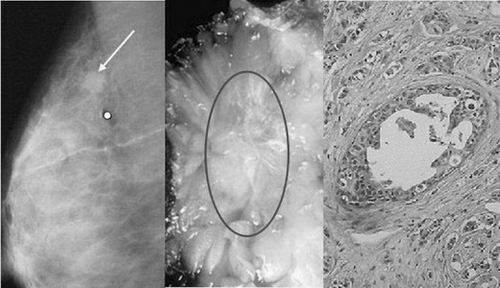

乳腺肿瘤早期检测微波热声医疗平台克服了常规检测方法低分辨率、低对比度、存在电离辐射等问题,利用不同生物组织在微波激励下介电常数和电导率的差异响应为指导,实现对小型乳腺肿瘤(<0.5cm)的有效检测。

目前,该平台在微波热声系统设计、传感器阵列布局设计优化、定量微波热声层析成像理论与方法、多维影像重建等关键技术均有突破性进展,现已成功用于小白鼠体内小型肿瘤(<1cm)的检测,并取得良好效果。